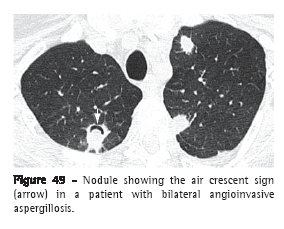

Air crescent sign (sinal do crescente aéreo)The air crescent sign corresponds to a collection of air of variable size and in the form of a crescent or half moon, located in the periphery of a nodule or mass and presenting soft tissue density; in the proper clinical context, this finding is suggestive of angioinvasive aspergillosis in the recovery phase (Figure 49).(77-79) In this case, the air crescent sign is secondary to the retraction of infarcted pulmonary parenchyma and the resorption of necrotic tissue in the peripheral region of the lesion, causing the space between the dead tissue and the adjacent parenchyma to be filled by air.(78) This sign is also used to describe the findings of the fungus ball, in which there is a collection of air surrounding the intracavitary lesion or interposed between the upper wall of the preexisting cavity and the hanging intracavitary lesion (Figure 7).(7) The air crescent sign has also been described in other diseases, such as intracavitary hemorrhage, bacterial abscess and lung cancer.(80,81)